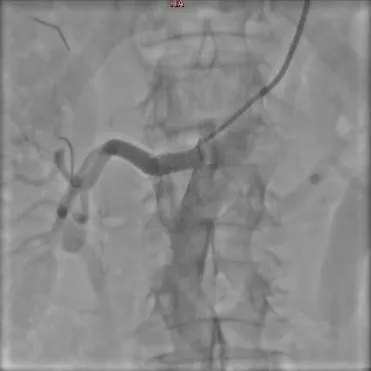

3. Контрольная ангиография

После операции пациенту необходимо принимать лекарственную терапию, назначенную врачом, в течение определенного времени. Своевременное стентирование стенозов почечных артерий позволяет сохранить полноценную функцию почечной паренхимы, а также уменьшить количество принимаемых гипотензивных препаратов.